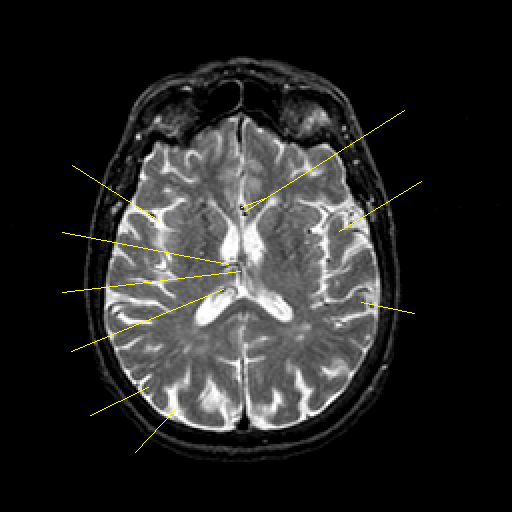

T2-weighted structural MR: Slice 30

Slice 30

Pointers

Labeled